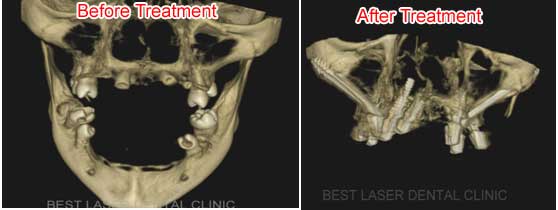

CASE REPORT OF PATIENT WITH ECTODERMAL DYSPLASIA TREATED BY

ZYGOMA IMPLANTS

Before and After 3D -CBCT Images